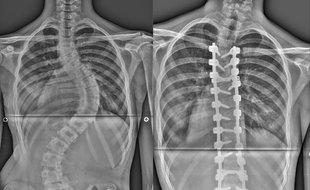

Dnes uplynulo 20 let od otevření Centra nemocí páteře a pohybového aparátu v Karvinské hornické nemocnici. Toto úzce specializované pracoviště se zabývá komplexní problematikou chirurgického ošetření nemocí celé páteře. V rámci České republiky je jedním ze tří pracovišť, které pravidelně provádí operace dětských skolióz, a rovněž se řadí do sítě 22 akreditovaných spondylochirurgických pracovišť.

Oddělení je už 17 let akreditovaným spondylochirurgickým pracovištěm. Tuto akreditaci uděluje Česká spondylochirurgická společnost, založená v roce 1999. Rozhodujícím faktorem pro udělení akreditace je počet provedených operací páteře na daném pracovišti. Smyslem sítě akreditovaných pracovišť je centralizace páteřní operativy do specializovaných center.